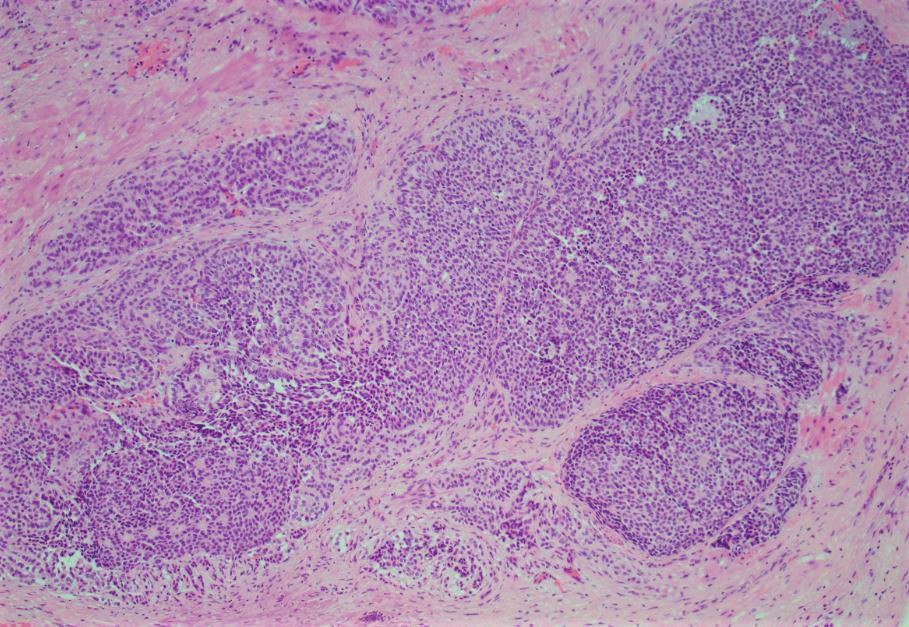

Answer: D. Granulosa cell tumor, adult type.

These tumors account for approximately 10% of sex cord stromal tumors and about 2 to 3% of all primary ovarian cancers.  These are low-grade malignant tumors that typically present as an adnexal mass in a peri-or postmenopausal woman.  These tumors can be associated with estrogenic manifestations such as disordered proliferative endometrium or endometrial hyperplasia and even endometrioid adenocarcinomas.  A small percentage of cases present as a result of tumor rupture and hemoperitoneum.

Histologically, the neoplastic cells comprising these neoplasms show scant cytoplasm and oval to angulated nuclei with prominent nuclear grooves such as in this case.  Architecturally, these neoplasms can present in a wide variety of histologic patterns.

AGCTs are typically reactive for inhibin and calretinin and are negative for EMA.  Additionally, these neoplasms were shown to have a single-point mutation in the FOXL2 gene.